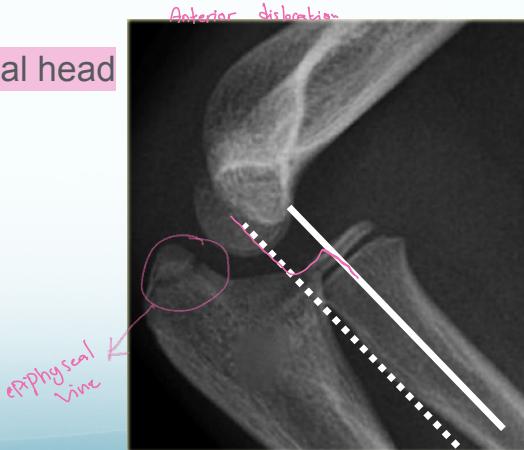

Radio-Capitellar Line:

- A line drawn through the center of the radial neck should pass through the center of the capitellum in all views and in both Extension and Flexion

- If not: dislocated radial head